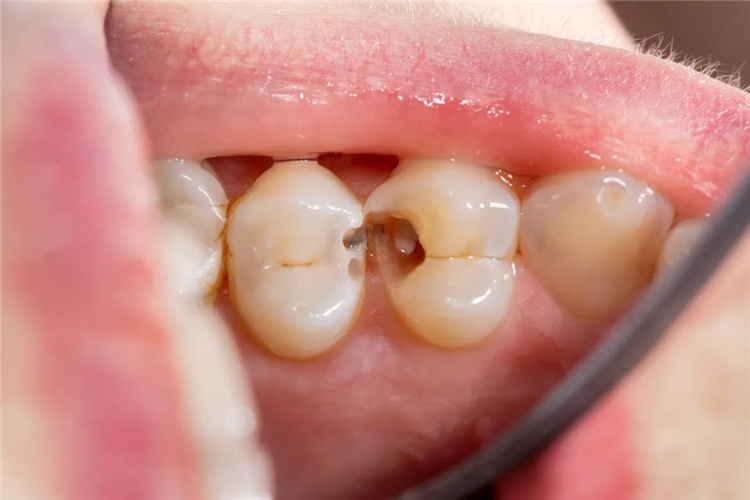

[蛀牙] 早发现早治疗

蛀牙不会自己好,吃药也没用。

蛀牙刚开始可能只是偶尔有细微的冷热不适,但如果不及时治疗,症状会加重,侵犯神经,很容易发展成为不可复性牙髓炎,带来持续不断的疼痛,甚至形成根尖的脓肿。

建议在年前做个全面口腔检查,如发现蛀牙,应尽快治疗,不要随意乱用消炎药,这些药物只能缓解表面症状,不及早治疗,牙齿缺损面积过大,无法一次性修补,不仅牙齿受罪,钱包也要受罪了。